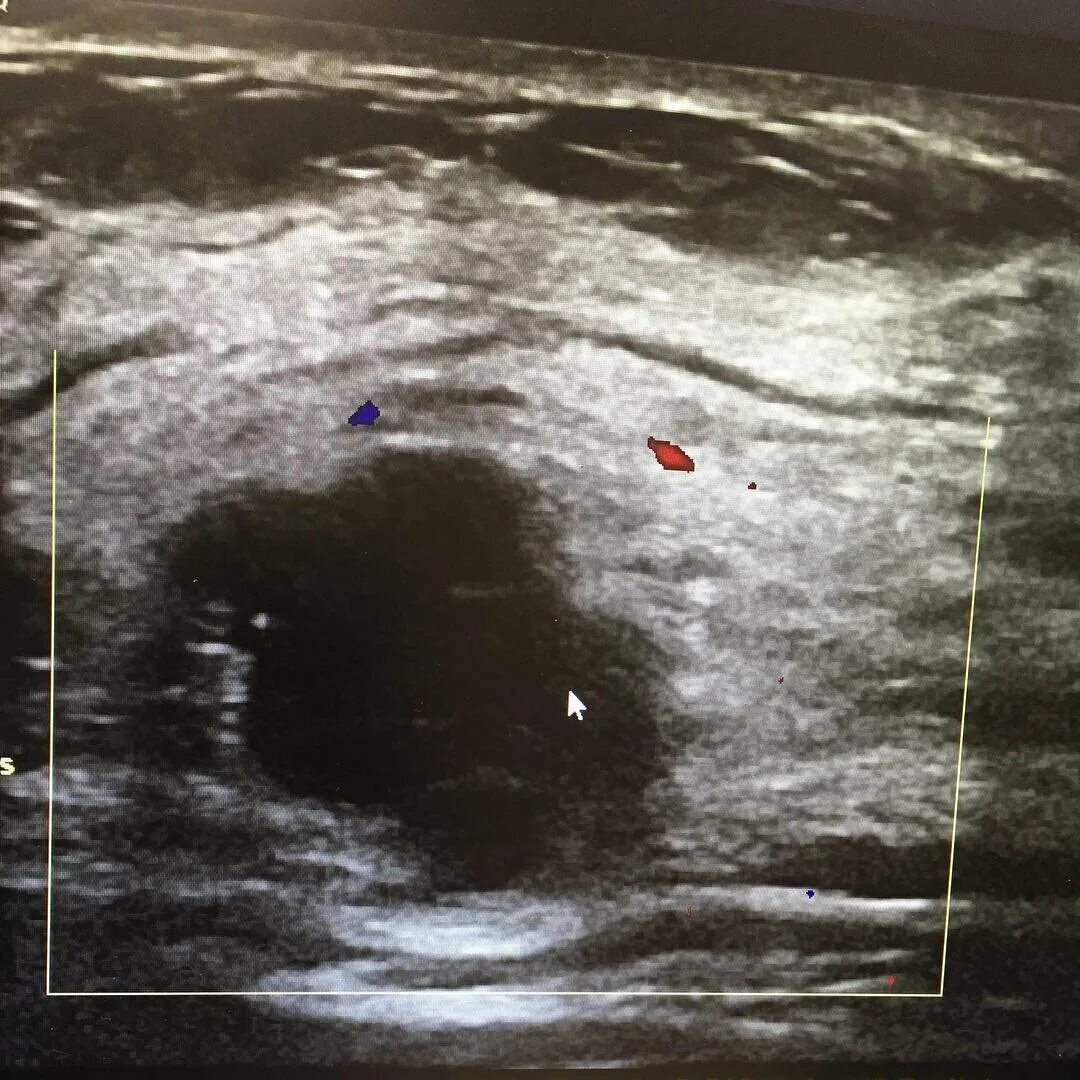

Уплотнения молочных желез форум